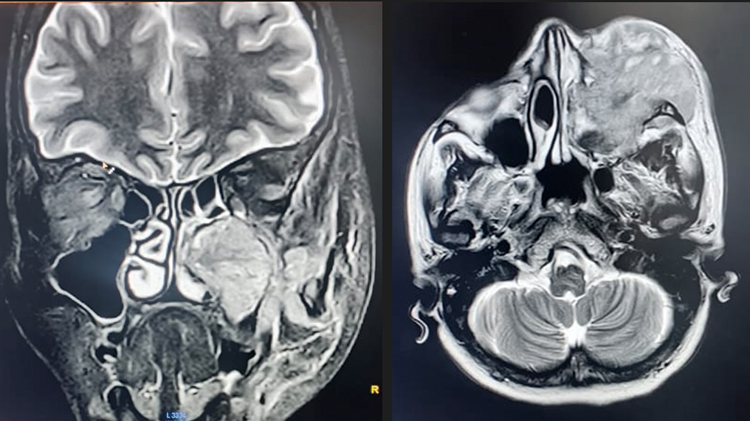

Diagnostic nasal endoscopy showed bulge in left lateral wall obliterating middle meatus with blood stained mucoid discharge in nasal cavity. Contrast enhanced CT and MRI scan of brain (Figure 3) showed heterogeneously enhancing lesion in left maxillary sinus with extension into orbit, nasal cavity, infratemporal fossa, superior alveolar process of maxilla, inferior orbital fissure and infiltration of maxillary division of trigeminal nerve with extensive bone destruction (Figure 2).

Figure 3. Contrast enhanced MRI brain